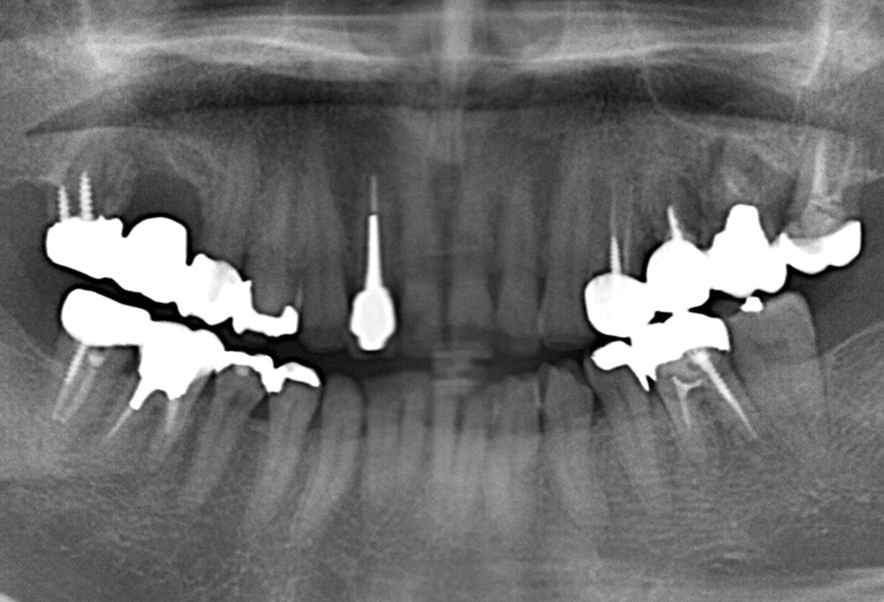

症例

Before

After

インプラント骨造成